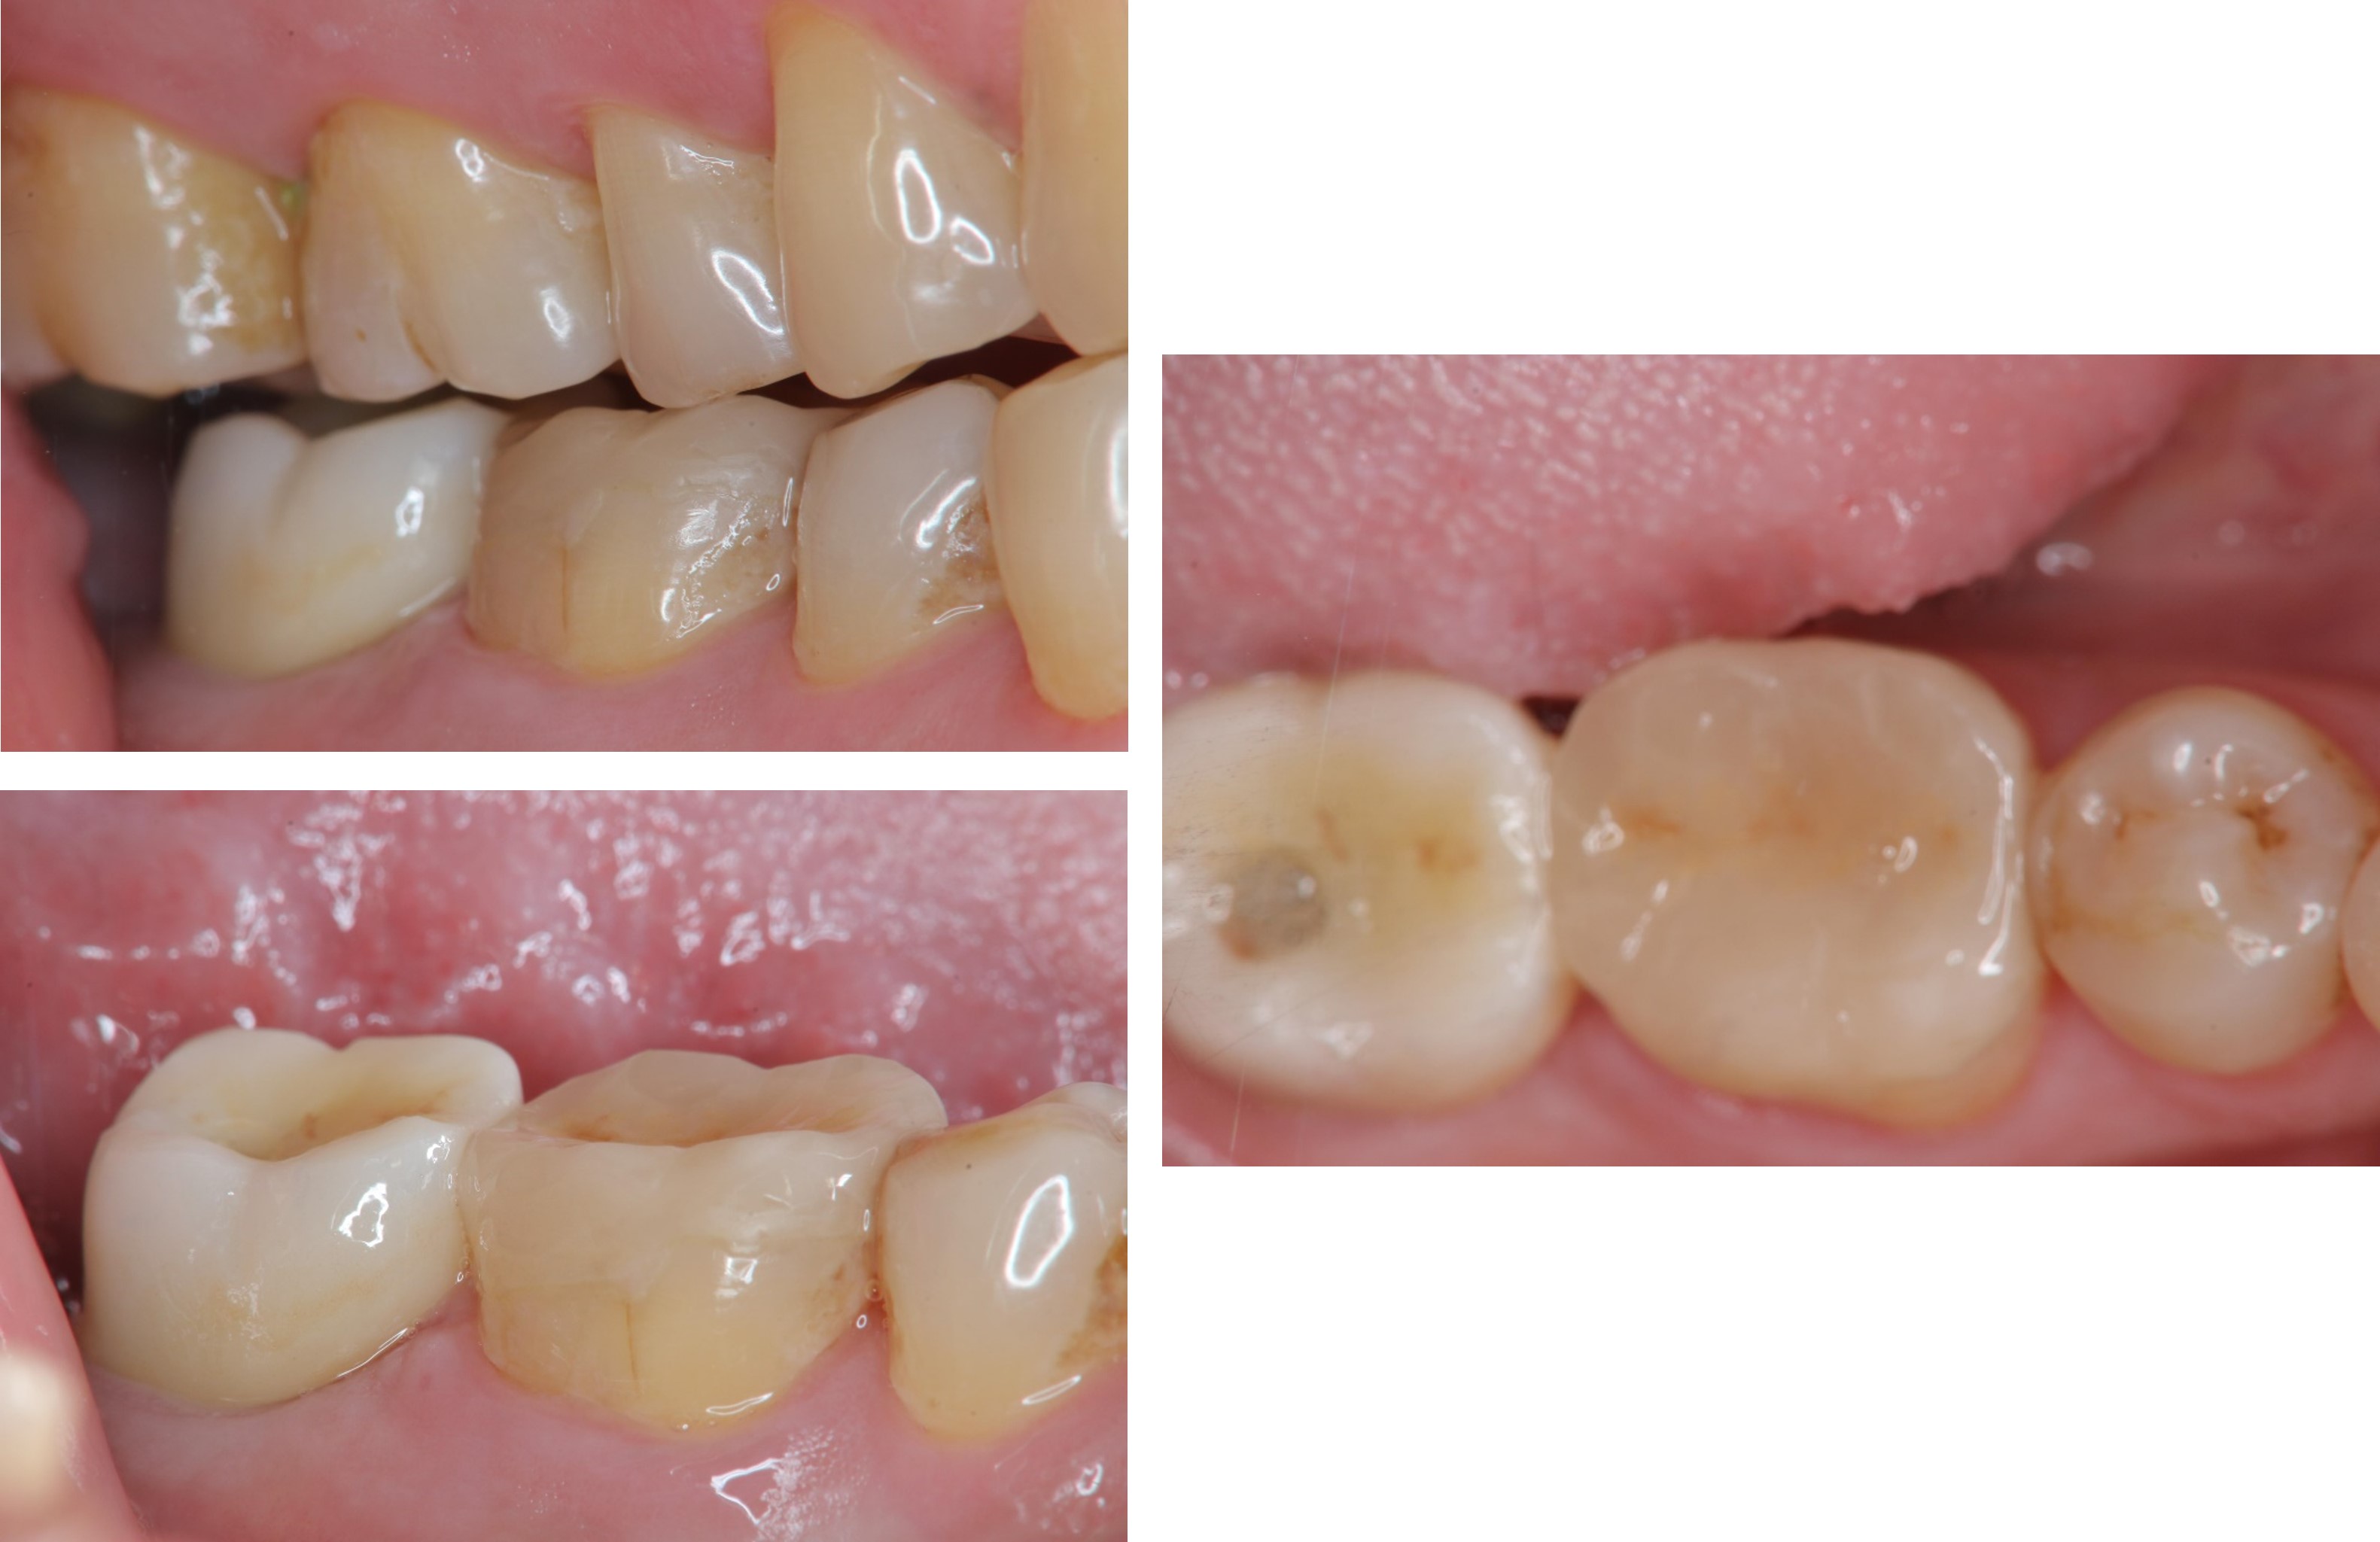

貼面邊緣完整

無殘膠存在

術前、術後比較

當蛀牙破壞程度大

陶瓷冠塊體是根據蛀牙的窩洞量身訂做,不管是顏色、精密度都是最佳的選擇,因此是非常美觀與持久的填補窩洞材料與技術